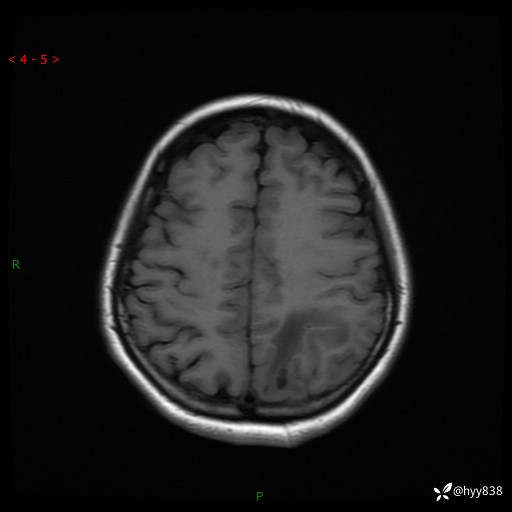

颅脑MRI平扫+增强